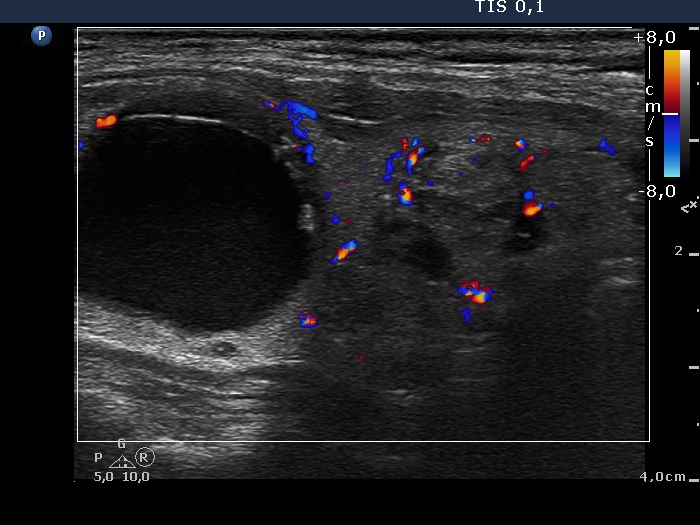

Intranodular hyperechogenic figures - case 662 (ultrasonographic picture 6)

Lower part of the right lobe, longitudinal scan, color Doppler mode. The hyperechogenic nodule presents signs of combined intranodular and perinodular vascular pattern.